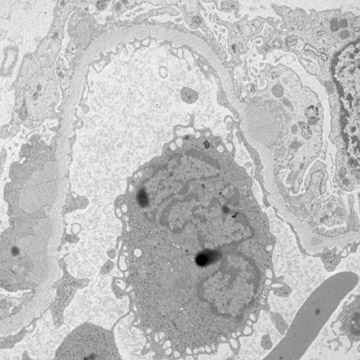

| By electron microscopy, the immune deposits of post-infectious glomerulonephritis are predominantly subepithelial, as seen above with electron dense subepithelial "humps" above the basement membrane and below the epithelial cell. The capillary lumen is filled with a leukocyte demonstrating cytoplasmic granules. Another example is shown below illustrating the subepithelial deposits. |